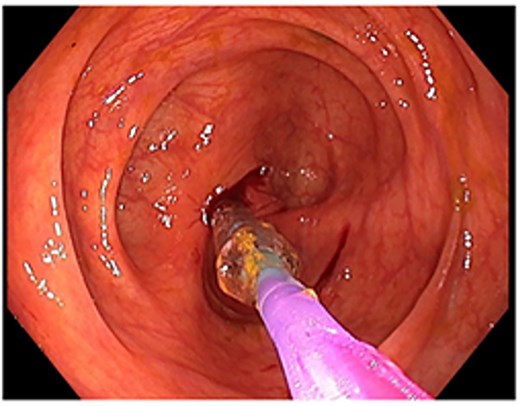

A 48-year-old lady with a background history of chronic migraines and family history of Crohn’s Disease presented to the emergency department with a three-day history of worsening abdominal pain and obstipation. She underwent a colonoscopy three days prior, which demonstrated shallow ulceration in the rectum and distal colon as well as a web-like stenosis in the ascending colon, 60 cm from the anal verge. The stenotic region was <5 mm in size and was unable to be traversed by the colonoscope, suspicious for a newly diagnosed stricturing Crohn’s disease (Fig. 1). She admitted to taking indomethacin suppositories 100 mg daily over the last two years for her migraines, as well as propranolol, triptan, ondansetron and sertraline. On examination her abdomen was soft, and tender in the right paraumbilical region without peritonism. Her haemoglobin was 94 g/L (115–165 g/L), C reactive protein (CRP) demonstrated a moderate inflammatory process at 40 mg/L (< 5 mg/L). Serum biochemistry and white cells were within normal limits. Computed tomography (CT) demonstrated a stricture in the ascending colon with an evolving proximal large bowel obstruction (Fig. 2). There was faecalisation in the terminal ileum suggestive of an acute on chronic obstruction. There was no suggestion of gastrointestinal perforation, or metastatic disease. The patient was made nil by mouth and prescribed intravenous hydrocortisone 100 milligrams four times a day by the gastroenterologist for suspected Crohn’s disease. However, the patient failed to progress after four days of hydrocortisone. A colonoscopic balloon dilatation was attempted with a 6 mm balloon, however the stricture appeared well-established, and the site began to bleed after the first attempt (Fig. 3). Subsequent attempts were abandoned due to the risk of bowel perforation. The distal end of the stricture was tattooed using spot ink. A colorectal surgeon became involved in her care who recommended a laparoscopic right hemicolectomy.

Attempted dilatation with a 6 mm balloon. The procedure was aborted after bleeding commenced.